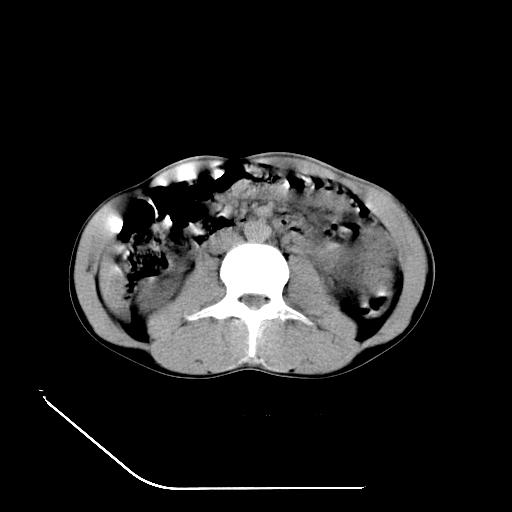

m-25y 高空堕落 12 月5号

12月7号病人尿量200ml/24h 急查双肾ct

左肾挫裂伤并肾周血肿;

肝肾间隙可见液区,建议手术探查;

左肾挫裂伤并肾周血肿

支持 : 左肾挫裂伤并肾周血肿

支持:1、左肾挫裂伤并肾周血肿;

2、少量腹水;

3、左肾旋转不良;

4、反射性肠淤张。

反射性肠郁张是指许多原因造成肠道吸收气体和液 功能障碍,也可造成分泌功能与动力的障碍,以致肠道内有过量的气体和液体潴积,有时只有过量的气体潴积。肠道较舒张,但不扩大,或有部分肠道轻度的扩大,这种情况叫做反射性肠郁张 ,这个病人的肠管扩张太明显了。

提示有肠梗阻的可能性?

除了1:左肾挫裂伤并肾周血肿;

2:少量腹水

第二次ct检查后:临床医生腹水穿刺后考虑肠系膜动脉破裂,后实行剖腹探查:于空肠距离十二指肠90cm处发现肠管破裂,破裂口较小;修补后关腹。